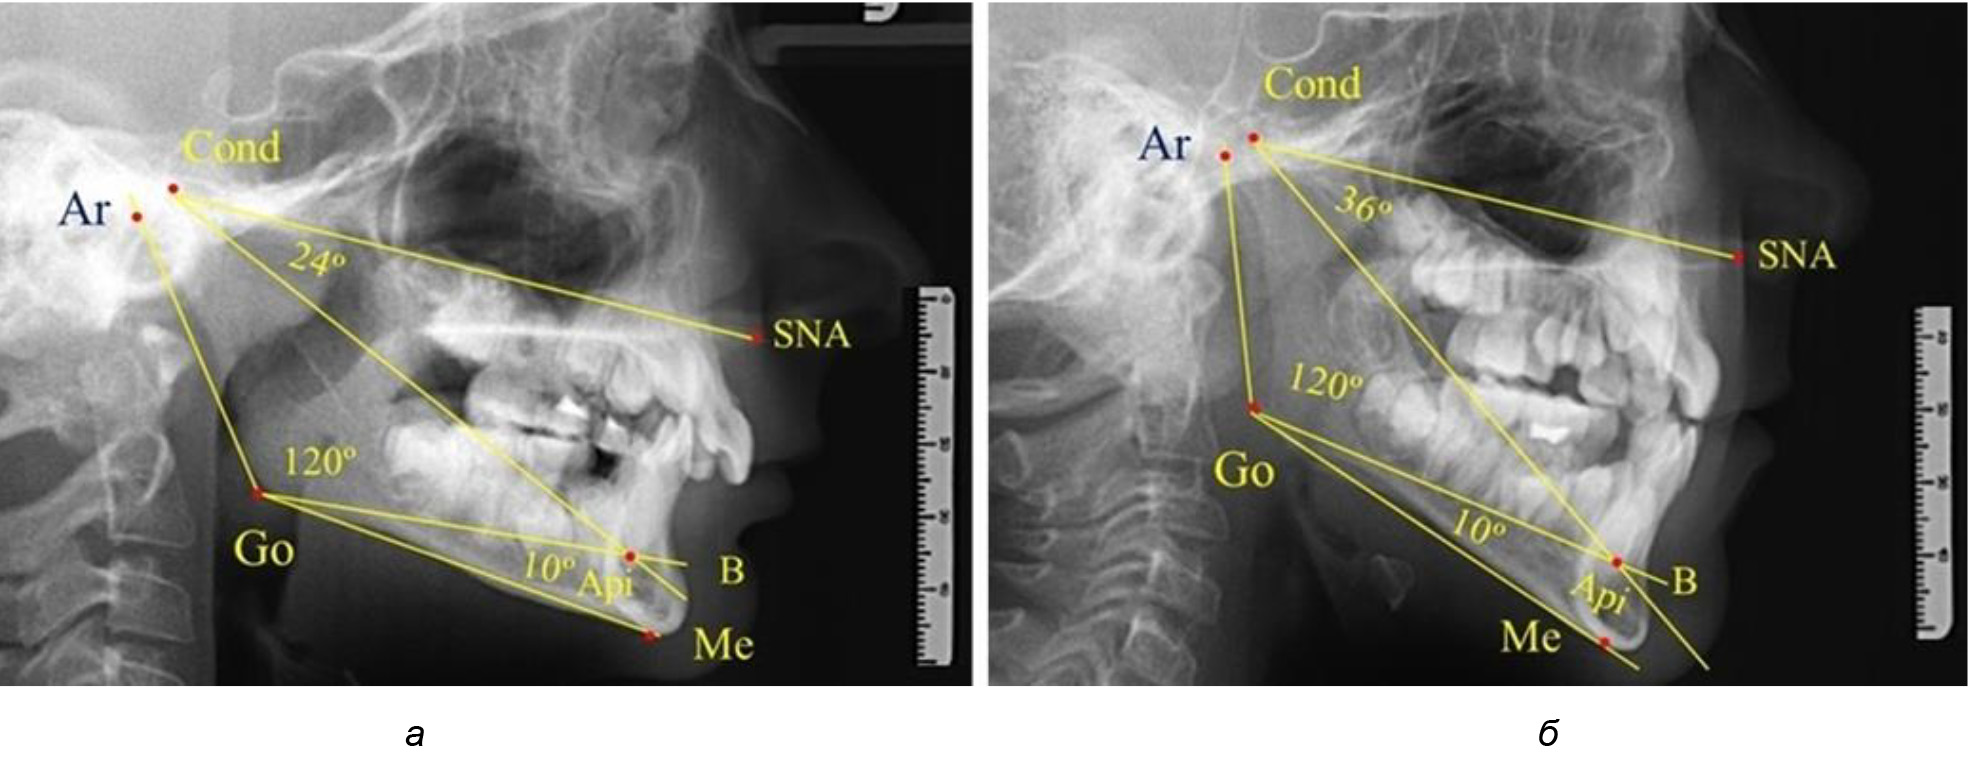

Проведен анализ 28 ТРГ молодых пациентов с физиологической окклюзии. На 13 рентгенограммах были признаки нейтрального роста лица, у 6 человек был вертикальный тип, а у 9 – горизонтальный тип лица.

В результате исследования телерентгенограмм людей в периоде сформированного постоянного прикуса выявлено, что величина угла гнатической части лица SNA-Cond-Api в среднем по группе составил (29,96 ± 0,84)°. При анализе рентгенограмм с разными типами нижнечелюстного угла Ar-Go-Me достоверных различий величины угла гнатической части лица нами не отмечено и при физиологической окклюзии показатели варьировали от 27 до 33°, что определяло оптимальные параметры гнатического отдела лица.

В то же время нижнечелюстной угол варьировал в широких пределах, в частности от 112 до 127°, и его средние значения при физиологическом прикусе составляли (120,57 ± 1,43)°. При этом составляющие части нижнечелюстного угла имели различия. Так, показатель угла Ar-Go-Api варьировал от 110 до 117°, при средних значениях – (107,12 ± 1,73)°. Величина угла Api-Go-Me составляла в среднем (13,56 ± 1,09)° при минимальных значениях 6° и максимальном показатели 19°. Анализируя параметры нижнечелюстного угла на телерентгенограммах с различными типами нижнечелюстного угла, выявлено, что у людей с нейтральными типами угла (в пределах от 119 до 123°) средний показатель был (121,83 ± 0,62)°. Величина угла Ar-Go-Api составила (107,89 ± 1,62)°, а угол Api-Go-Me был (13,83 ± 1,12)°.

При вертикальном типе нижнечелюстного угла его средние значения составили (125,51 ± 0,44)°, и достоверно отличалась от показателей людей с нейтральными значениями нижнечелюстного угла. Величина угла Ar-Go-Api составила (115,49 ± 2,14)°, а угол Api-Go-Me был (13,97 ± 1,26)°.

Для горизонтального типа роста было характерно достоверное р ˂ 0,05 уменьшение нижнечелюстного угла до (115,57 ± 0,56)°. Величина угла Ar-Go-Api составила (102,71 ± 1,62)°, а угол Api-Go-Me был (12,86 ± 0,74)° (рис. 3).

Рис. 3. Особенности ТРГ при нейтральном (а), вертикальном (б) и горизонтальном (в) типе угла нижней челюсти в постоянном прикусе

Таким образом, вне зависимости от величины нижнечелюстного угла, показатели угла гнатической части лица были в пределах 30°, что может расцениваться в качестве оптимального физиологического показателя параметров гнатической части лица. Анализ ТРГ проведен у 31 ребенка в различные периоды дентального онтогненеза, включая прикус молочных зубов и различные группы прорезывания постоянных зубов.